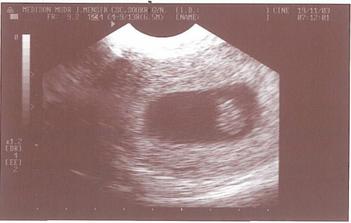

17.11.2008 mimísek nás trochu postrašil, přišlo špinění a trochu krve a proto jsme jeli na pohotovost, kde nás uklidnili a dokonce jsme poprvé viděli krásně blikat jeho srdíčko :o)) důvodem špinění je hematom :o(

20.11.2008 první poradna u doktora - srdíčko bylo krásně vidět, hematom se vstřebává a dostali jsme těhu průkazku hurááá, byl nám nasazen Utrogestan, taky proběhla fotečka a samozřejmě odběry atd. příští kontrola bude 11.12.2008